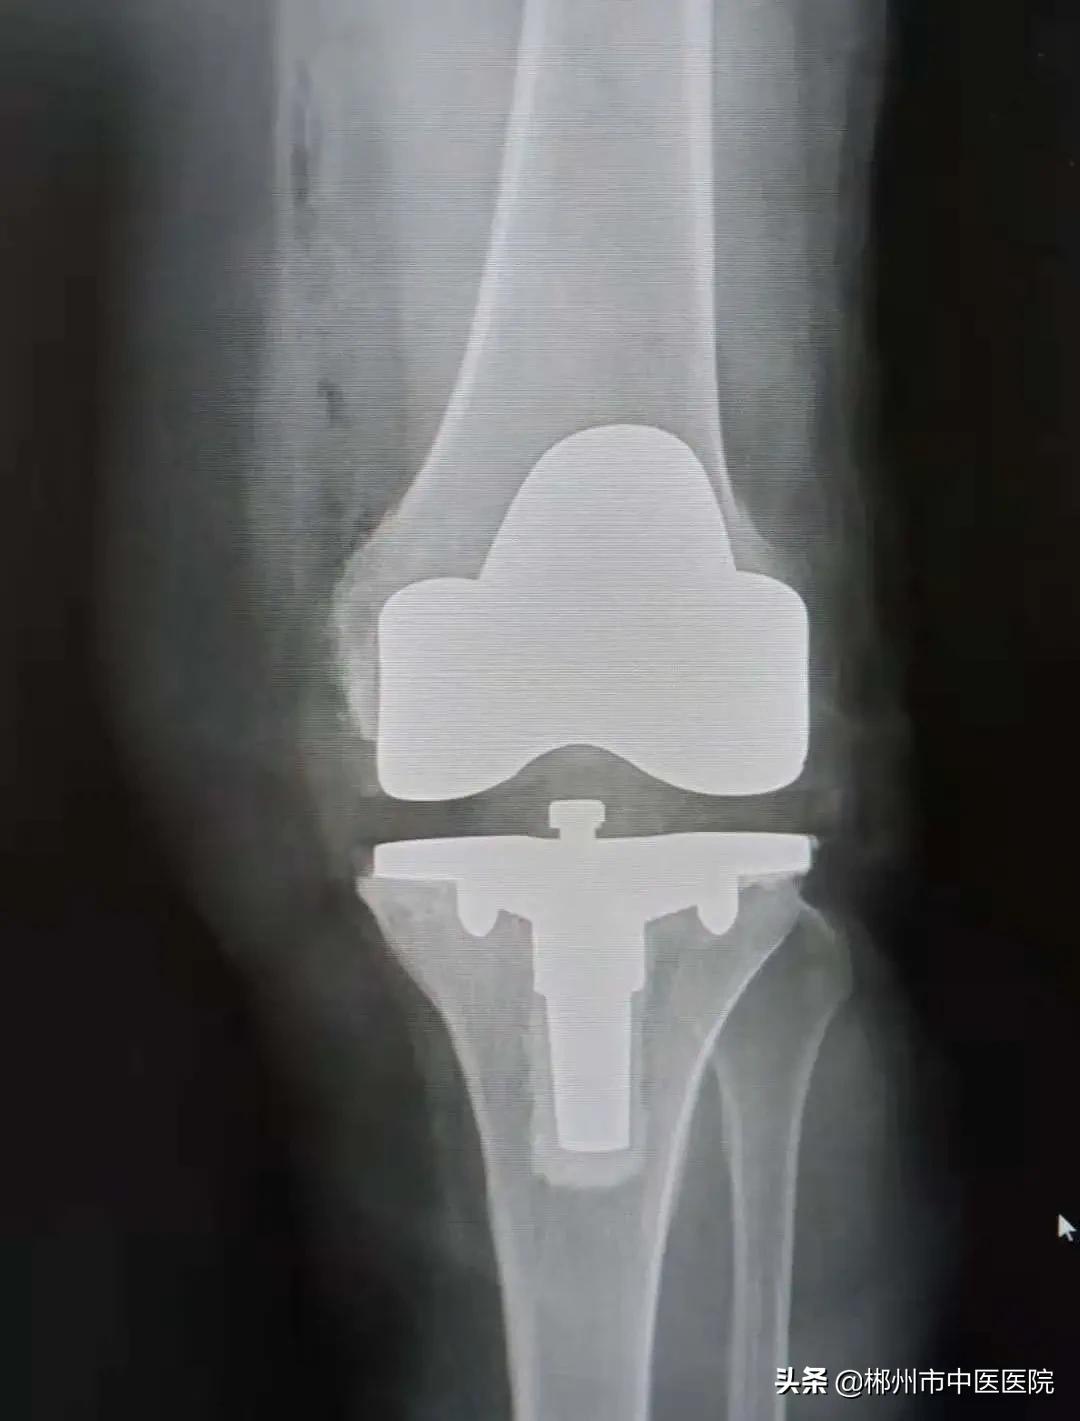

通过安装人工膝关节假体,解决了李奶奶膝关节内翻畸形问题,纠正了下肢力线。

术后X线片情况

术后第二天,李奶奶下肢屈曲可达120度,伸直0度,可辅助助步器下地行走,复查DR片显示膝关节假体间隙平衡。